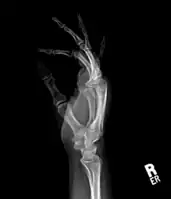

Medical imaging usually shows a well-defined wide-based bony growth on the surface of bone.[5] It can be pedunculated and irregular, giving it a "bizarre" appearance, and is not connected to underlying bone.[2]

X-ray hand, BPOP 2nd metacarpal -

X-ray hand, BPOP 2nd metacarpal (side view)